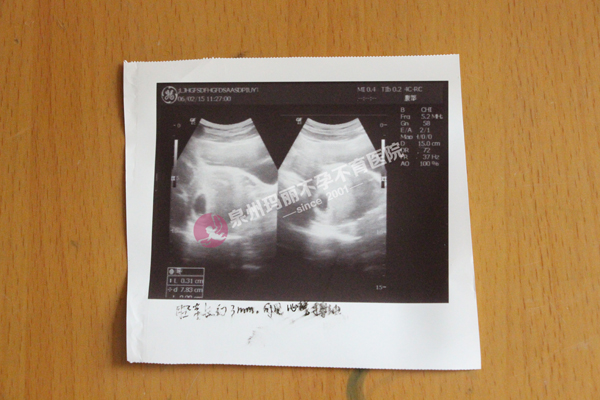

(刘女士怀孕B超单)

2015年3月24日,她和老公一起来到泉州玛丽医院。李心茹主任为他们接诊,在了解了他们的详细情况之后,李主任建议她和她老公同时做检查。玛丽医院一直以来都倡导夫妻同诊模式,不孕不育的原因不一定是出在女性身上,夫妻同诊能更快速准确的查明病因。于是,他们夫妻二人都进行了检查,结果显示她有输卵管一侧上举、一侧堵塞以及多囊卵巢的问题,她的老公于保文有精子不液化、弱精问题。这才是导致他们夫妻二人多年不孕的原因,李主任建议于保文进行中药调理,玉英则进行“腹腔镜打孔”和“三镜一丝”手术。“腹腔镜打孔”能有效的改善以往治疗技术的弊端,更加直观的治疗女性多囊卵巢,做到精准、高效、无创、可靠;“三镜一丝”手术通过联合运用输卵管镜、宫腔镜、腹腔镜“三镜”和黑泥鳅智能导丝“一丝”,一次性有效介入,准确检测卵巢、宫腔、腹腔、输卵管腔内外病变,并且同步全面解决子宫、卵巢盆腔与输卵管积水、粘连与堵塞等问题。夫妻俩人听从了李主任的建议,进行了手术治疗,术后也调养了一段时间。5月初,玉英就发现自己怀孕了!